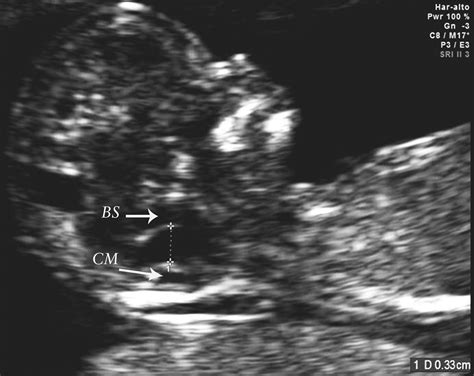

• Measuring the nuchal translucency (NT) thickness, which is the fluid-filled space at the back of the baby’s neck. This measurement helps in assessing the risk of chromosomal abnormalities such as Down syndrome.

At 14 weeks, the fetus undergoes significant developmental changes. Some of the key milestones include:

• The baby’s head is still large in proportion to the body, but the body is starting to catch up.

• The baby’s limbs are more defined, and the fingers and toes are visible.

• The baby’s facial features are becoming more distinct, with eyes moving closer together and ears almost in their final position.

• The baby’s heart is beating strongly, and the lungs are starting to form.

• The baby’s digestive system is developing, and the intestines are moving from the umbilical cord to the abdomen.